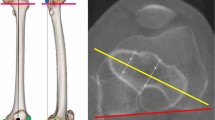

IMN holes laser indicator in animal tests

Measurements were performed on 10 animal samples, 5 sheep's legs, and 5 cows' legs which were supplied from the Zarrinshahr slaughterhouse, Iran. Sheep's samples had a small diameter between 16 and 21 mm and a large diameter between 29 and 35 mm. Also, the cows' samples had a small diameter between 40 and 48 mm and a large diameter between 65 and 73 mm. For each sample, intramedullary nailing (Pooyandegan Pezeshki Pardis-Golestan-Iran) was performed inside the tibia bone, and distal locking was done three times using the laser intramedullary nail holes indicator. Figure 4, shows intramedullary nailing procedures for one of the samples.

During evaluating the IMN holes laser indicator in a human test, by inserting the probe inside the IMN, the light passing through the nail holes in the proximal region was more intense than in the distal region as shown in schematic image Fig. 9B. Moreover, the diameter of the circle created on the patient's foot due to the passing of light in the distal was smaller than the proximal. However, the diameter of the foot is larger in the proximal, and we should have seen less light passing through this region. As shown in Fig. 9C, the cortex in the proximal of the tibia bone has a small thickness and a large diameter. Approaching the distal, the thickness of the cortex increases, and the diameter of the tibia bone decreases. Therefore, the tibia bone is strong enough in a small diameter area. The cortex is denser than other parts of the bone. The passage of the beam through the dense area is more difficult than the less dense area. As a result, as approaching the distal of the tibia, the passage of the beam decreases so is observed a circle with a smaller diameter in the distal. By reducing the diameter of the circle, the position of the nail hole can be determined more accurately.